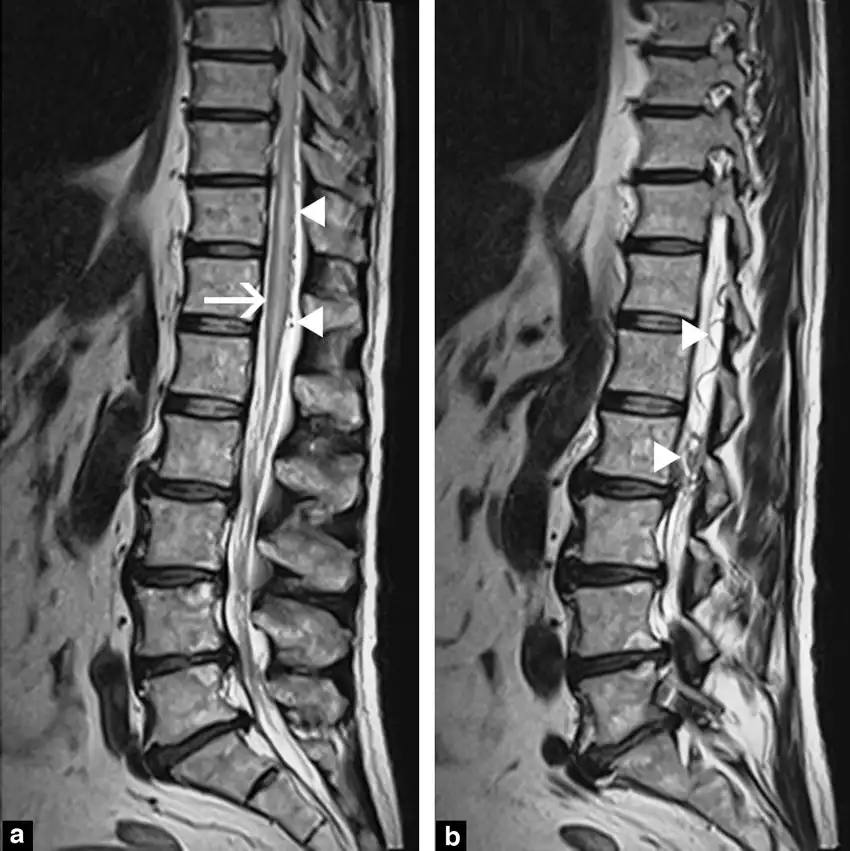

فیستول انتهای ستون فقرات با استفاده از معاینه فیزیکی، تصویربرداری (MRI، CT اسکن، میلوگرام) و آزمایشهای آزمایشگاهی (بررسی مایع مغزی نخاعی) تشخیص داده میشود.